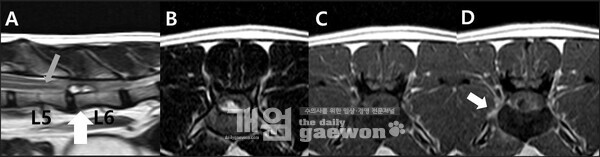

이번 논문은 요추 추간판 탈출증과 유사한 소견을 보인 고양이의 척수 경막외 수막종 증례를 다룬 연구로 기존에 주로 경막 내에서 발생하는 것으로 알려진 수막종이 경막 외 공간에서 발생한 사례를 영상 진단과 수술, 조직병리학적 분석을 통해 규명한 것이 특징이다.

연구에 따르면, 해당 증례는 MRI 검사에서 추간판 탈출증과 유사한 소견을 보여 감별 진단이 어려웠으나 후궁 절제술과 조직검사를 통해 섬유성 수막종으로 최종 확진됐다. 이러한 경막외 수막종은 매우 드문 형태로, 비전형적 척추 병변의 진단에 중요한 참고 사례가 될 것으로 평가된다.